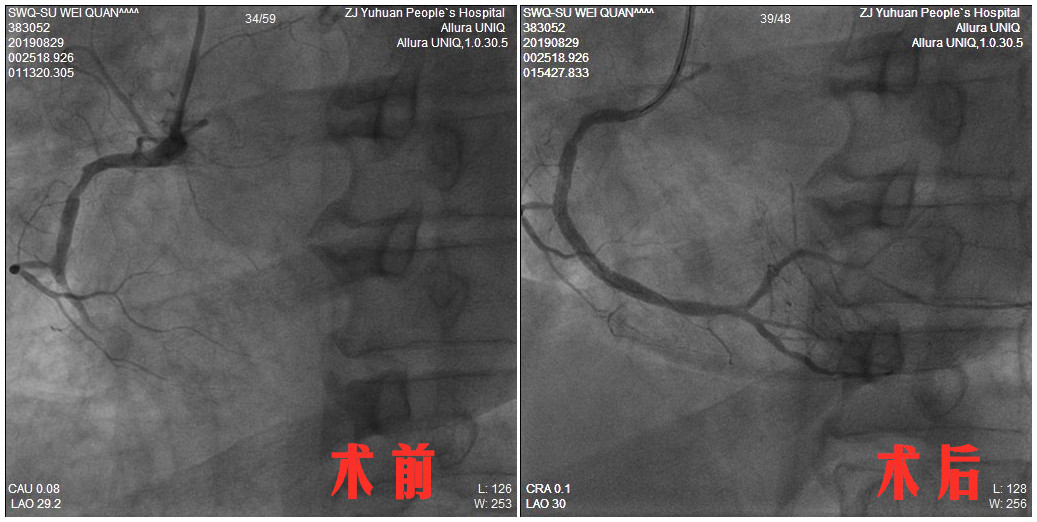

“患者心脏上的三根重要血管严重病变,右冠中段完全闭塞,前降支和回旋支多处狭窄90%左右,心脏血供极少。”叶如剑介绍,大面积的血管堵塞是险象环生的主要原因。长时间的手术患者无法耐受,这次手术按照“首要救命”原则,先在完全闭塞的右冠植入支架,待各项指征平稳,张老伯还需进行二次手术,在另外两根病变血管里放上支架。